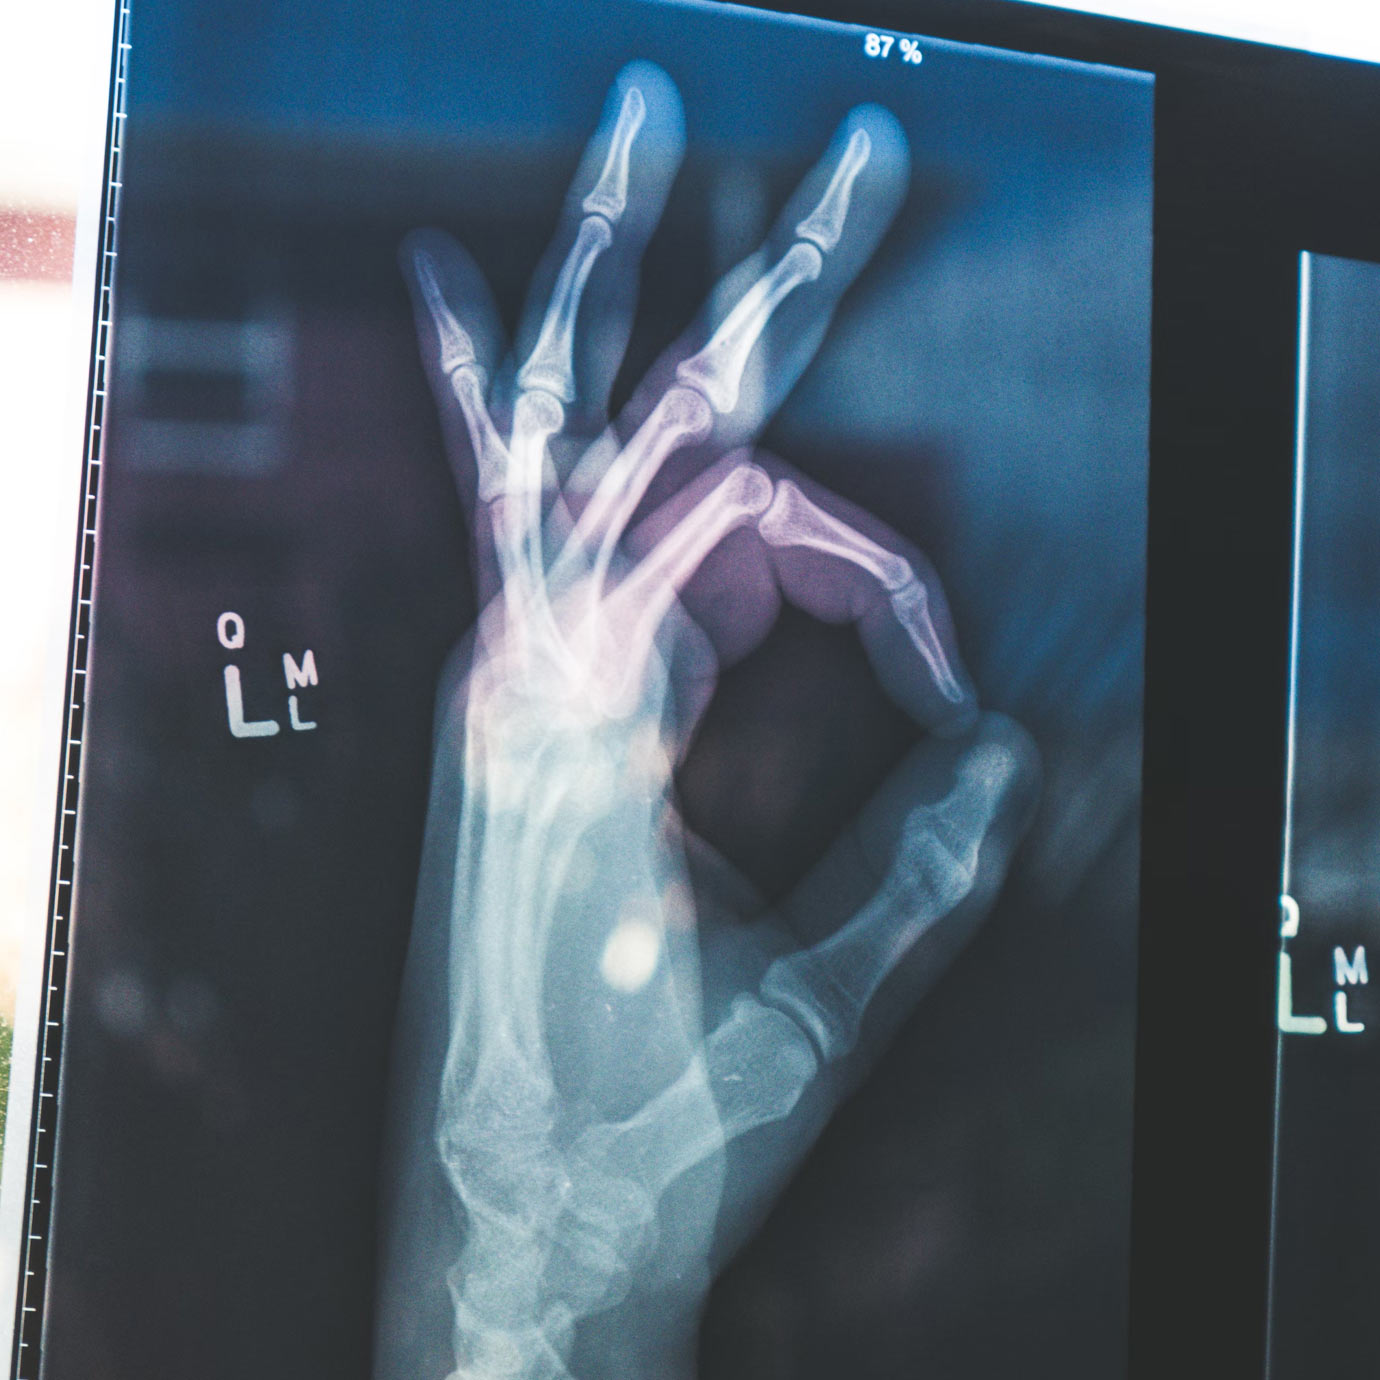

Pomocí umělé inteligence můžeme detekovat například rakovinu plic již v jejím samém počátku. V takovém případě je šance pacienta na přežití prvního roku více, než 87 %. Ve čtvrtém stadiu je pak méně, než 19 %.(1) Bez použití umělé inteligence v praxi je lékařova schopnost rozeznat z rentgenového snímku nálezy rakoviny plic v úvodních stadiích, kdy je nádor ještě velmi malých rozměrů, značně omezená, ve většině případů prakticky nemožná. (2)

Pomocí vizuálních map vás upozorní na možné nálezy na snímku, a je pouze na vás, jestli je potvrdíte. Pomůže lépe zvládnout neustále se navyšující počet vyšetření, které lékař musí vyhodnotit. Díky přímé implementaci do systémů, které běžně užíváte, nemusíte otevírat žádný další program, nebo aplikaci.